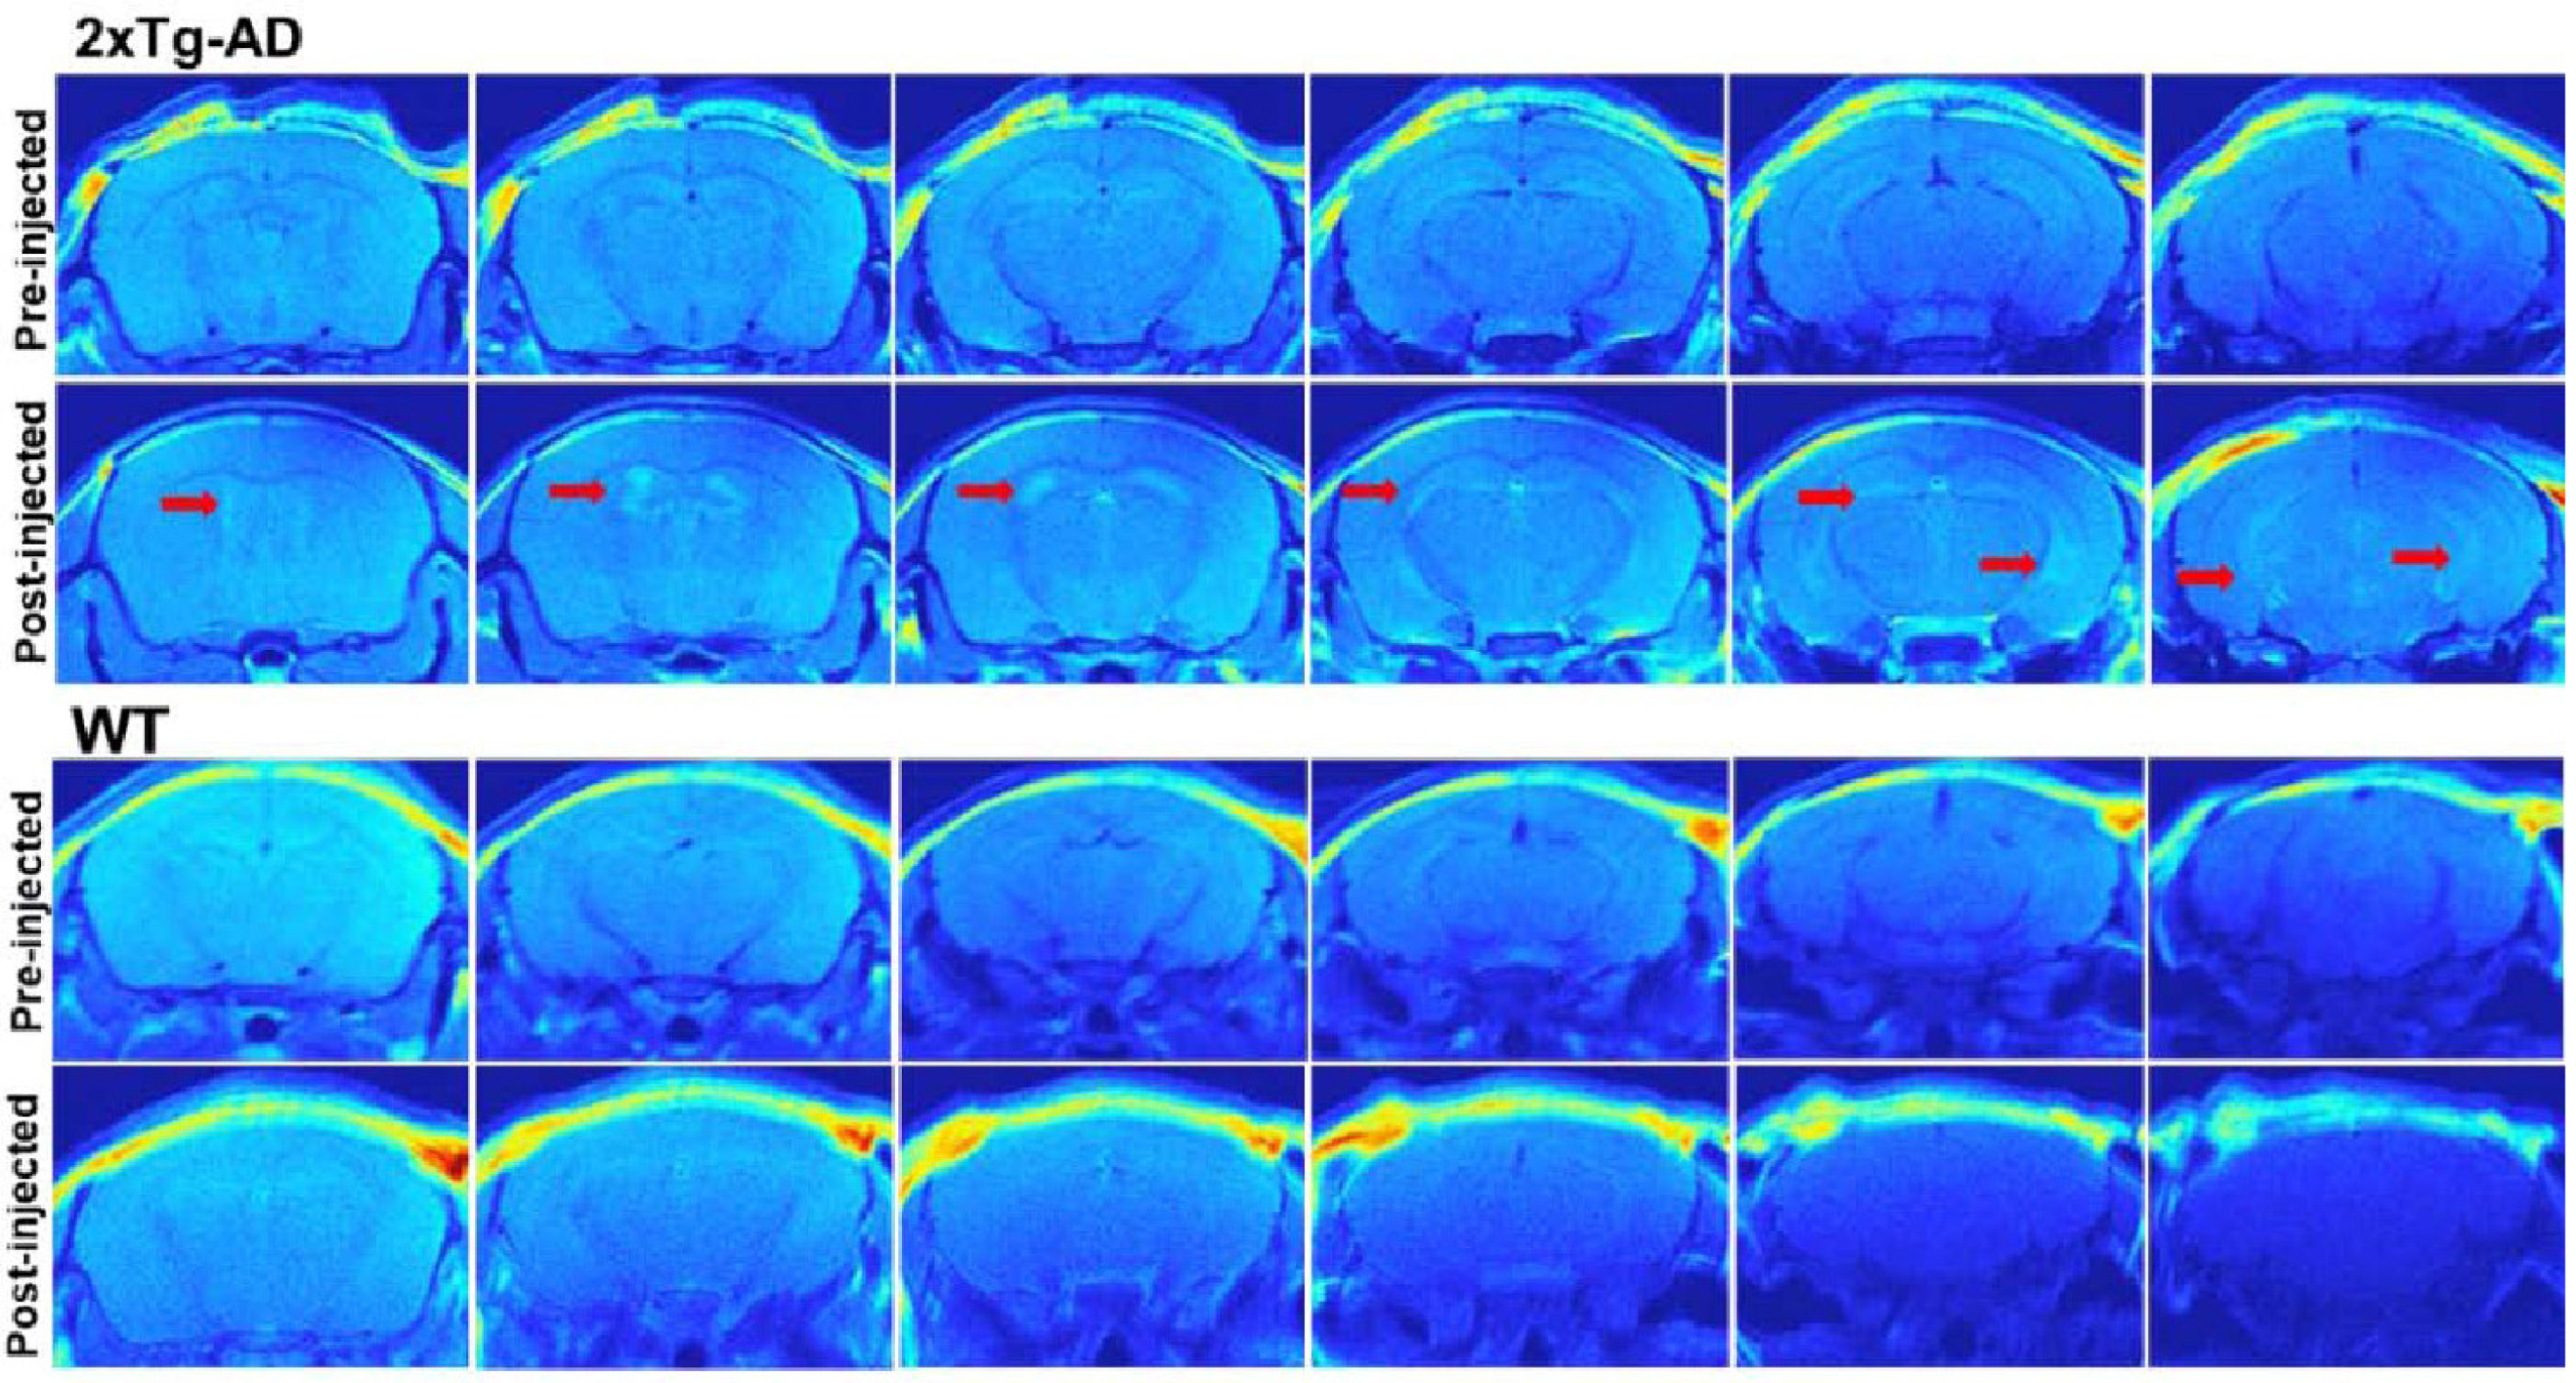

- Yanagisawa, D.; Amatsubo, T.; Morikawa, S.; Taguchi, H.; Urushitani, M.; Shirai, N.; Hirao, K.; Shiino, A.; Inubushi, T.; Tooyama, I. In Vivo Detection of Amyloid β Deposition Using 19F Magnetic Resonance Imaging with a 19F-Containing Curcumin Derivative in a Mouse Model of Alzheimer’s Disease. Neuroscience 2011, 184, 120–127. [Google Scholar] [CrossRef] [PubMed]

- Yanagisawa, D.; Taguchi, H.; Ibrahim, N.F.; Morikawa, S.; Shiino, A.; Inubushi, T.; Hirao, K.; Shirai, N.; Sogabe, T.; Tooyama, I. Preferred Features of a Fluorine-19 MRI Probe for Amyloid Detection in the Brain. J. Alzheimer’s Dis. 2014, 39, 617–631. [Google Scholar] [CrossRef] [PubMed]

- Yanagisawa, D.; Ibrahim, N.F.; Taguchi, H.; Morikawa, S.; Tomiyama, T.; Tooyama, I. Fluorine-19 Magnetic Resonance Imaging for Detection of Amyloid β Oligomers Using a Keto Form of Curcumin Derivative in a Mouse Model of Alzheimer’s Disease. Molecules 2021, 26, 1362. [Google Scholar] [CrossRef] [PubMed]